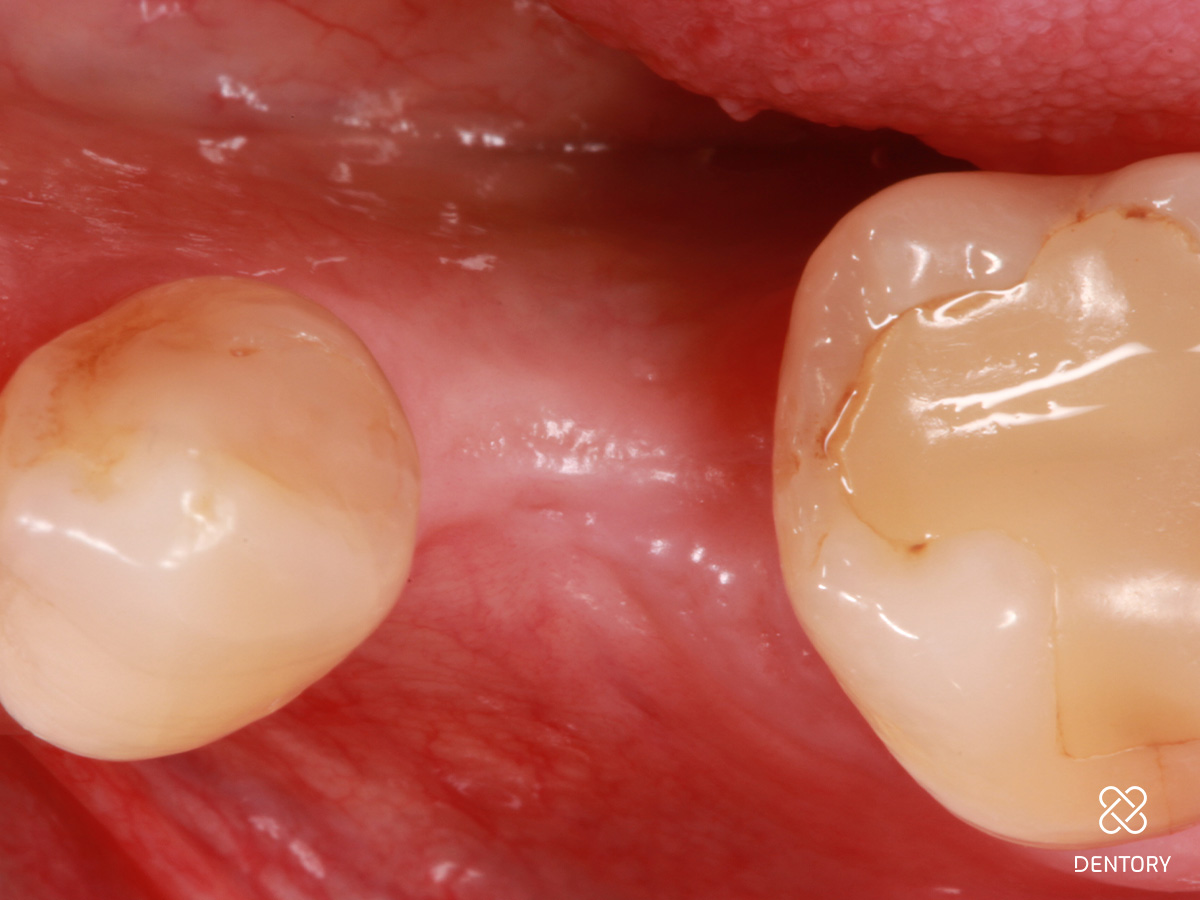

Abbildung 16

Situation vor dem Einsetzen der definitiven Rekonstruktion: Vor dem Einsetzen der definitiven Rekonstruktion zeigen sich gesunde Weichgewebsverhältnisse mit ausreichend befestigter Mukosa für stabile Knochenverhältnisse.